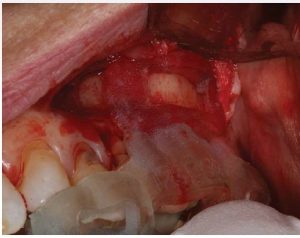

The cervical area of tooth LR3 was severely abraded. An intra -sulcular full-thickness muco-periosteal fap was raised; a vertical re leasing incision was positioned mesial to tooth LRI. The surgical stent was placed over the maxillary teeth (Figure 8) and a piezotome-guided surgical window wasdeveloped using the margins of the stent (Figure 9).

A chisel was used to elevate the cortical plate and root resection performed with Lindemann burs (Figure l0).

The cortical window was placed in sterile saline while the endodontic microsurgery was completed. After resection

using Lindemann burs, the root periphery was stained with methylene blue and examined for anomalies and the root canal space was retro-prepared with ultrasonic tips to a depth of three millimetres, creating a reservoir for the retro sealing materials.